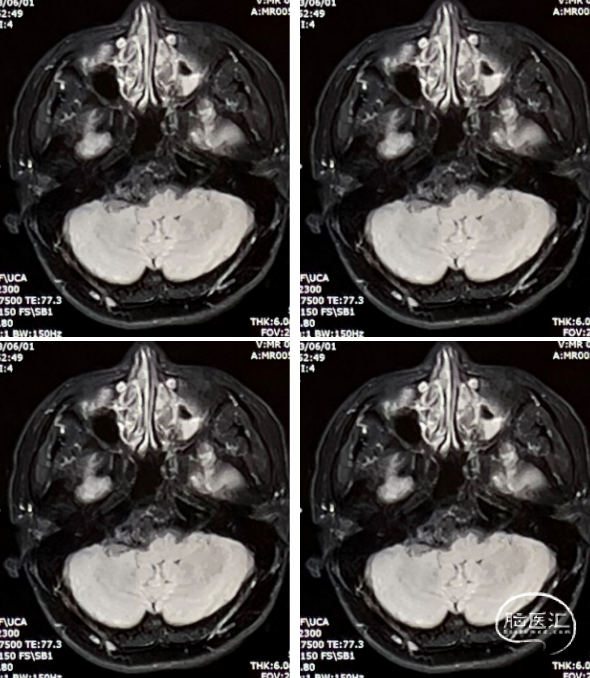

患者情况

查体:右侧听力下降。